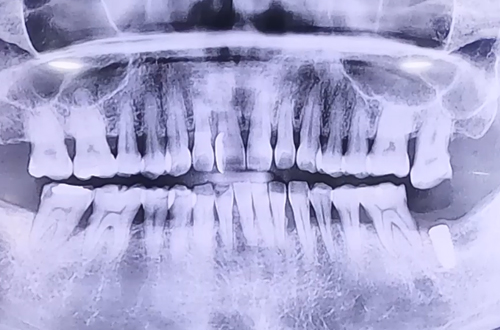

어금니 임플란트

BEFORE

왼쪽 아래 맨 뒤 큰 어금니 하나를 발치한지 오래된 환자분이십니다.

잇몸이 좋은 상태에서 임플란트 치료가 이루어진 만큼 수월하게 진행되었는데요.

아래 받쳐줘야 되는 치아가 없어 위에 치아가 중력에 의해 아래로 내려와 있는 부분은 옆에 치아들과 같은 높이로 올려주는 보철치료를 병행하며 임플란트 치료를 진행할 예정입니다.

아래쪽 임플란트가 뼈랑 단단하게 붙는 기간을 기다리고 난 뒤 3개월 후에 임플란트가 완성되면 다음 진료일지로 찾아뵙도록 하겠습니다! ^^